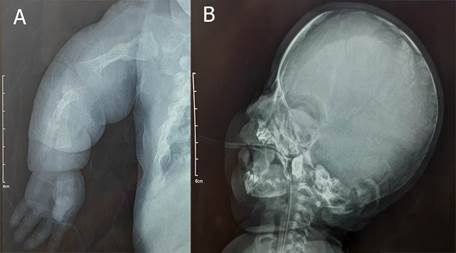

El diagnóstico en regiones alejadas del país es netamente clínico, debido a la carencia de exámenes genéticos y escasos recursos económicos de la familia para poder trasladarse a centros especializados; dichos factores son causantes de abandono de tratamiento. Si bien el diagn6stico definitivo es mediante secuenciaci6n genética; reportes de caso con diagnósticos clínicos y radiográficos de Osteogénesis imperfecta contribuyen a la data nacional y permiten que el hospital tenga un registro de la casuística presente, reemergente y emergente con mayor posibilidad de poder derivar a estos pacientes a los centros especializados para un estudio a profundidad (figura 4 y figura 5).

Figura 5. A. Radiografía postero-anterior de miembro superior izquierdo, micromelia, fractura consolidada de diáfisis de húmero, y deformidades angulares producto de fracturas, se evidencia fractura de húmero izquierdo consolidada, y fractura reciente de diáfisis cubital. B. Radiografía lateral de cráneo, en la cual se evidencia hipoplasia del hueso occipital.